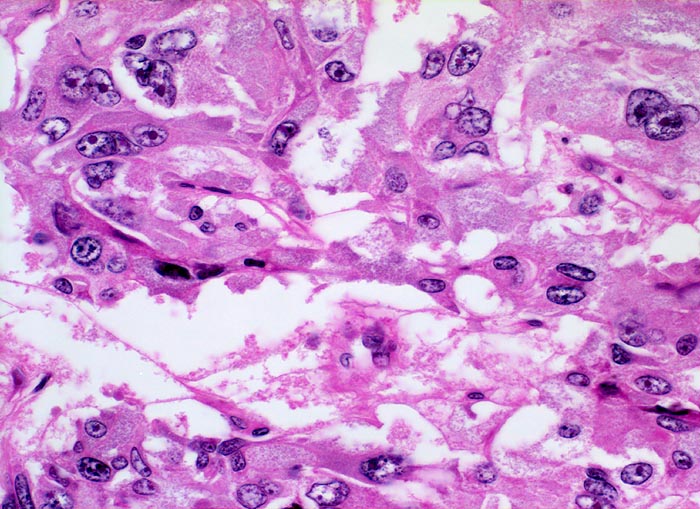

Phaeochromozytom

Die Tumorzellen zeigen hier deutliche Atypien. Ein Teil der Zellen hat mehrere stark vergrösserte Kerne mit vergröbertem Chromatin und vergrösserten Nukleolen.

Riesenzellen und Zellen mit bizarren Atypien lassen sich in Phaeochromozytomen/Paragangliomen oft fokal nachweisen. Atypien, Mitosen, lokal invasives Wachstum und Gefässinvasion können in gutartigen Tumoren vorkommen. Es gibt keine verlässlichen histologischen Kriterien, um benigne von malignen Phaeochromozytomen zu unterscheiden. Entscheidend ist der Nachweis bzw. das Fehlen von Metastasen.